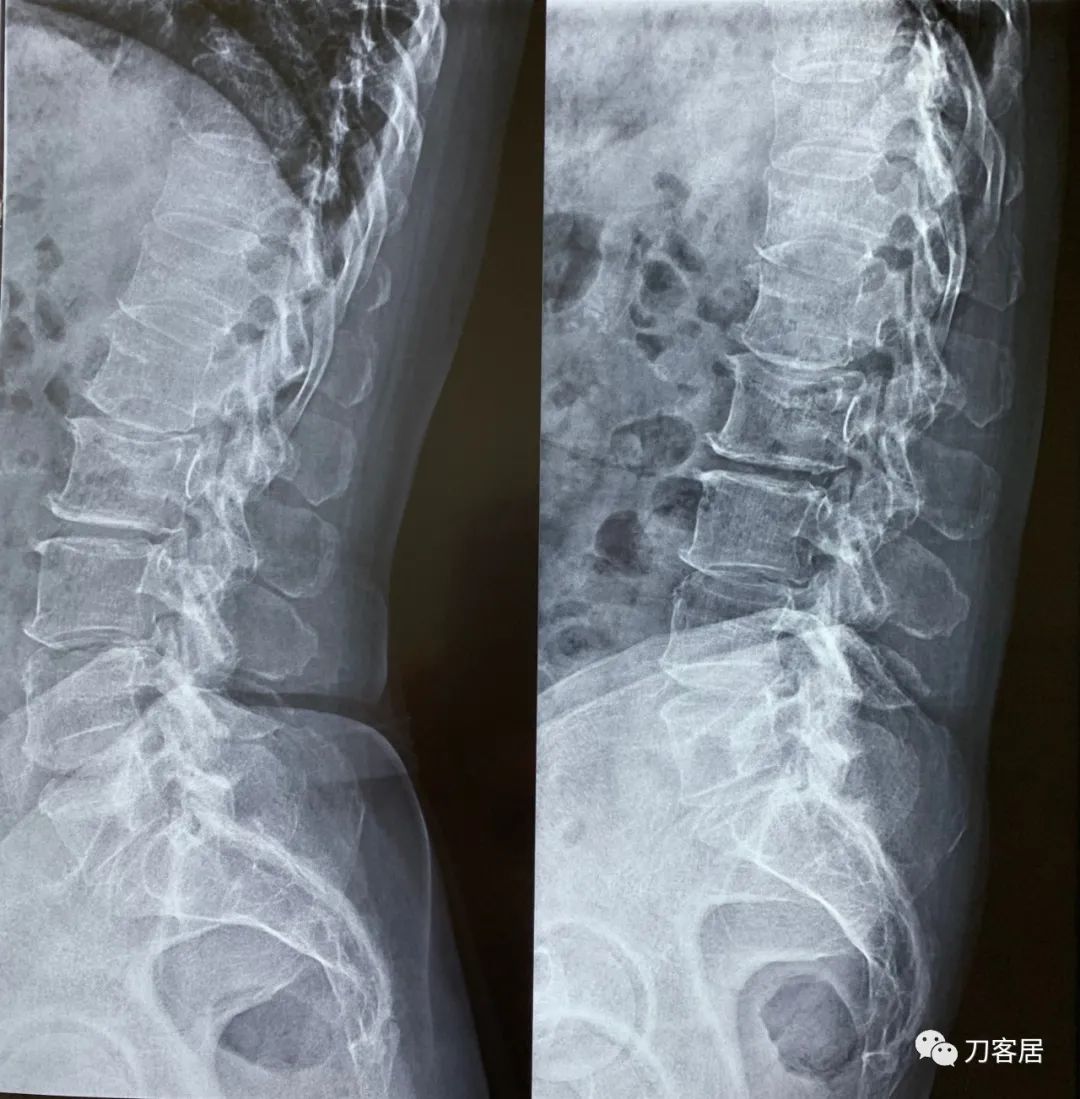

建议其查双光子骨密度,骨盆正位片以及腰椎间盘平扫。腰椎正侧位X线片以及动力位片,站立位脊柱全长正侧位X线片,以了解其是否有骨质疏松,并了解脊柱侧弯情况,腰椎局部X线表现情况和腰椎间盘突出和椎管狭窄情况。

从这个患者的影像资料分析,颈椎间盘突出问题不大,没有明确的上位神经元损伤表现,所以,不考虑颈椎和胸椎问题。腰椎侧弯畸形,但不严重。因为存在腰椎侧弯,使得腰椎MRI在扫描切面的时候,显示的椎间盘突出或椎管狭窄会有一定的误差,所以,又加做了经椎间盘的CT平扫,影像表现并不严重,综上,腰椎间盘突出,腰椎管狭窄,腰椎侧弯,不考虑手术治疗。同时,患者的主要痛苦是心理疾病,而不是器质性疾病,所以,以心身疾病治疗为主。虽然患者骨密度检查结果提示正常,但X线片显示骨质疏松,且其症状也与骨质疏松的症状有符合之处,比如静息痛,不能入睡,动作及姿势变换时痛加重等,所以,给予实验性抗骨质疏松治疗,以观疗效。